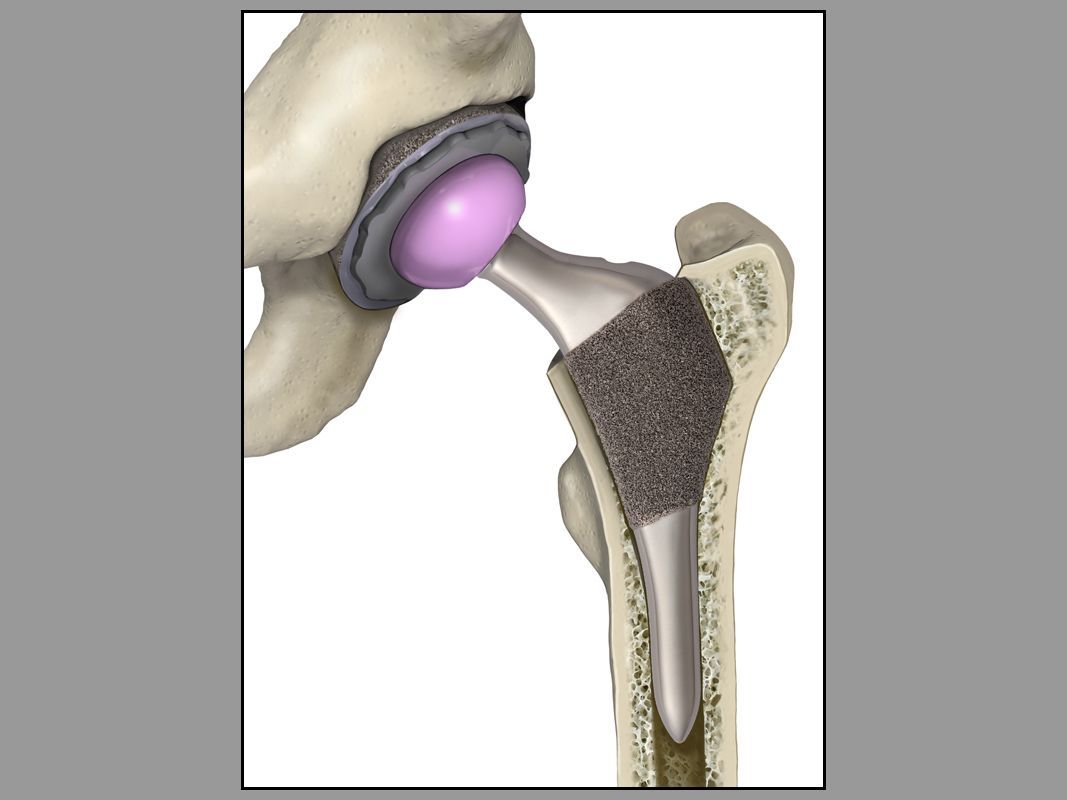

Total Hip Replacement

Series of illustrations to promote a medical device manufacturer's new total hip replacement.